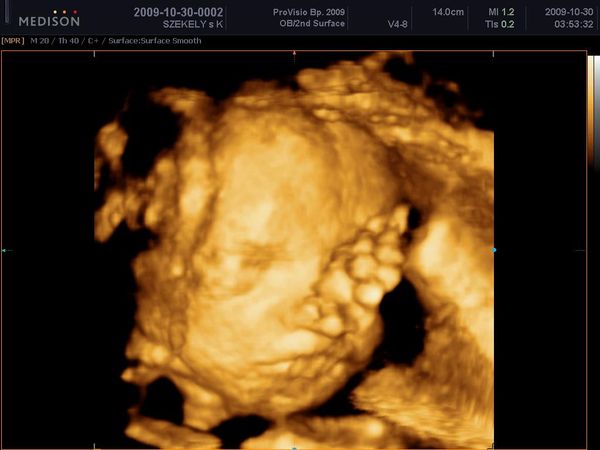

Uh: Hát már a végén voltunk, ezért kissé gyorsabban folyt a vizsgálat, mint Katicánál, de azért nagyon szuper volt. Láthattuk a babók arcát ÉÉÉÉÉÉÉÉÉÉÉÉÉÉÉÉéééééééééés sok újat megtudtunk:

- mindkét baba fejvégű már, tehát szülhetek természetes módon :D

- két lepény van, az eddig tudott egy helyett, ami nagyon jó - így mondjuk nem tudni, hogy egy vagy két petéjűek e

- de továbbra is mindketten fiúk :)

Méreteket sajna nem mértek, egy angol hölgy vizsgált, és a placentás dolog elmagyarázásához is kellett egy doki, aki roppant kedves volt :)

A babák most úgy fekszenek, hogy a nagyobb baba (Gergő) bal oldalon van, kissé lentebb, és kisebb baba (Bálint) búbja az ő mellkasán :) Inkább háttal a pocakomnak vannak, a gerincem felé fordulva, úh a nőci látta mennyire szenvedek háton, mondta hogy oldalra is fordulhatok. Jobb is volt, mert kezdtem begörcsölni.

Na és a képek mellett vannak kis videók is a cd-n :) bár van ami kétszer is megvan, de így is olyan jó :)

1. Gergő arc

2. Ketten együtt

3. Bálint arc (a szája elé sajnos belógott a köldökzsinór)